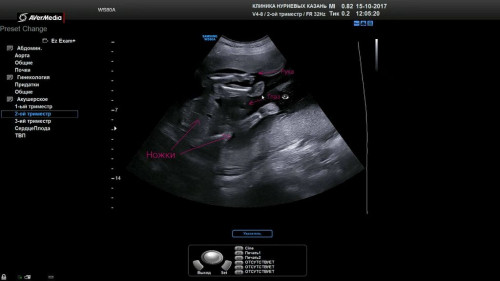

7).

мое тоже прикольное. Мои девочки валетиком лежат и палец вам показывает одна) особено супер фотогурманам)) 😂😂😂

Сейчас уже их положение совершенно другое. Прикольно оно мне, застали один единственный разок))